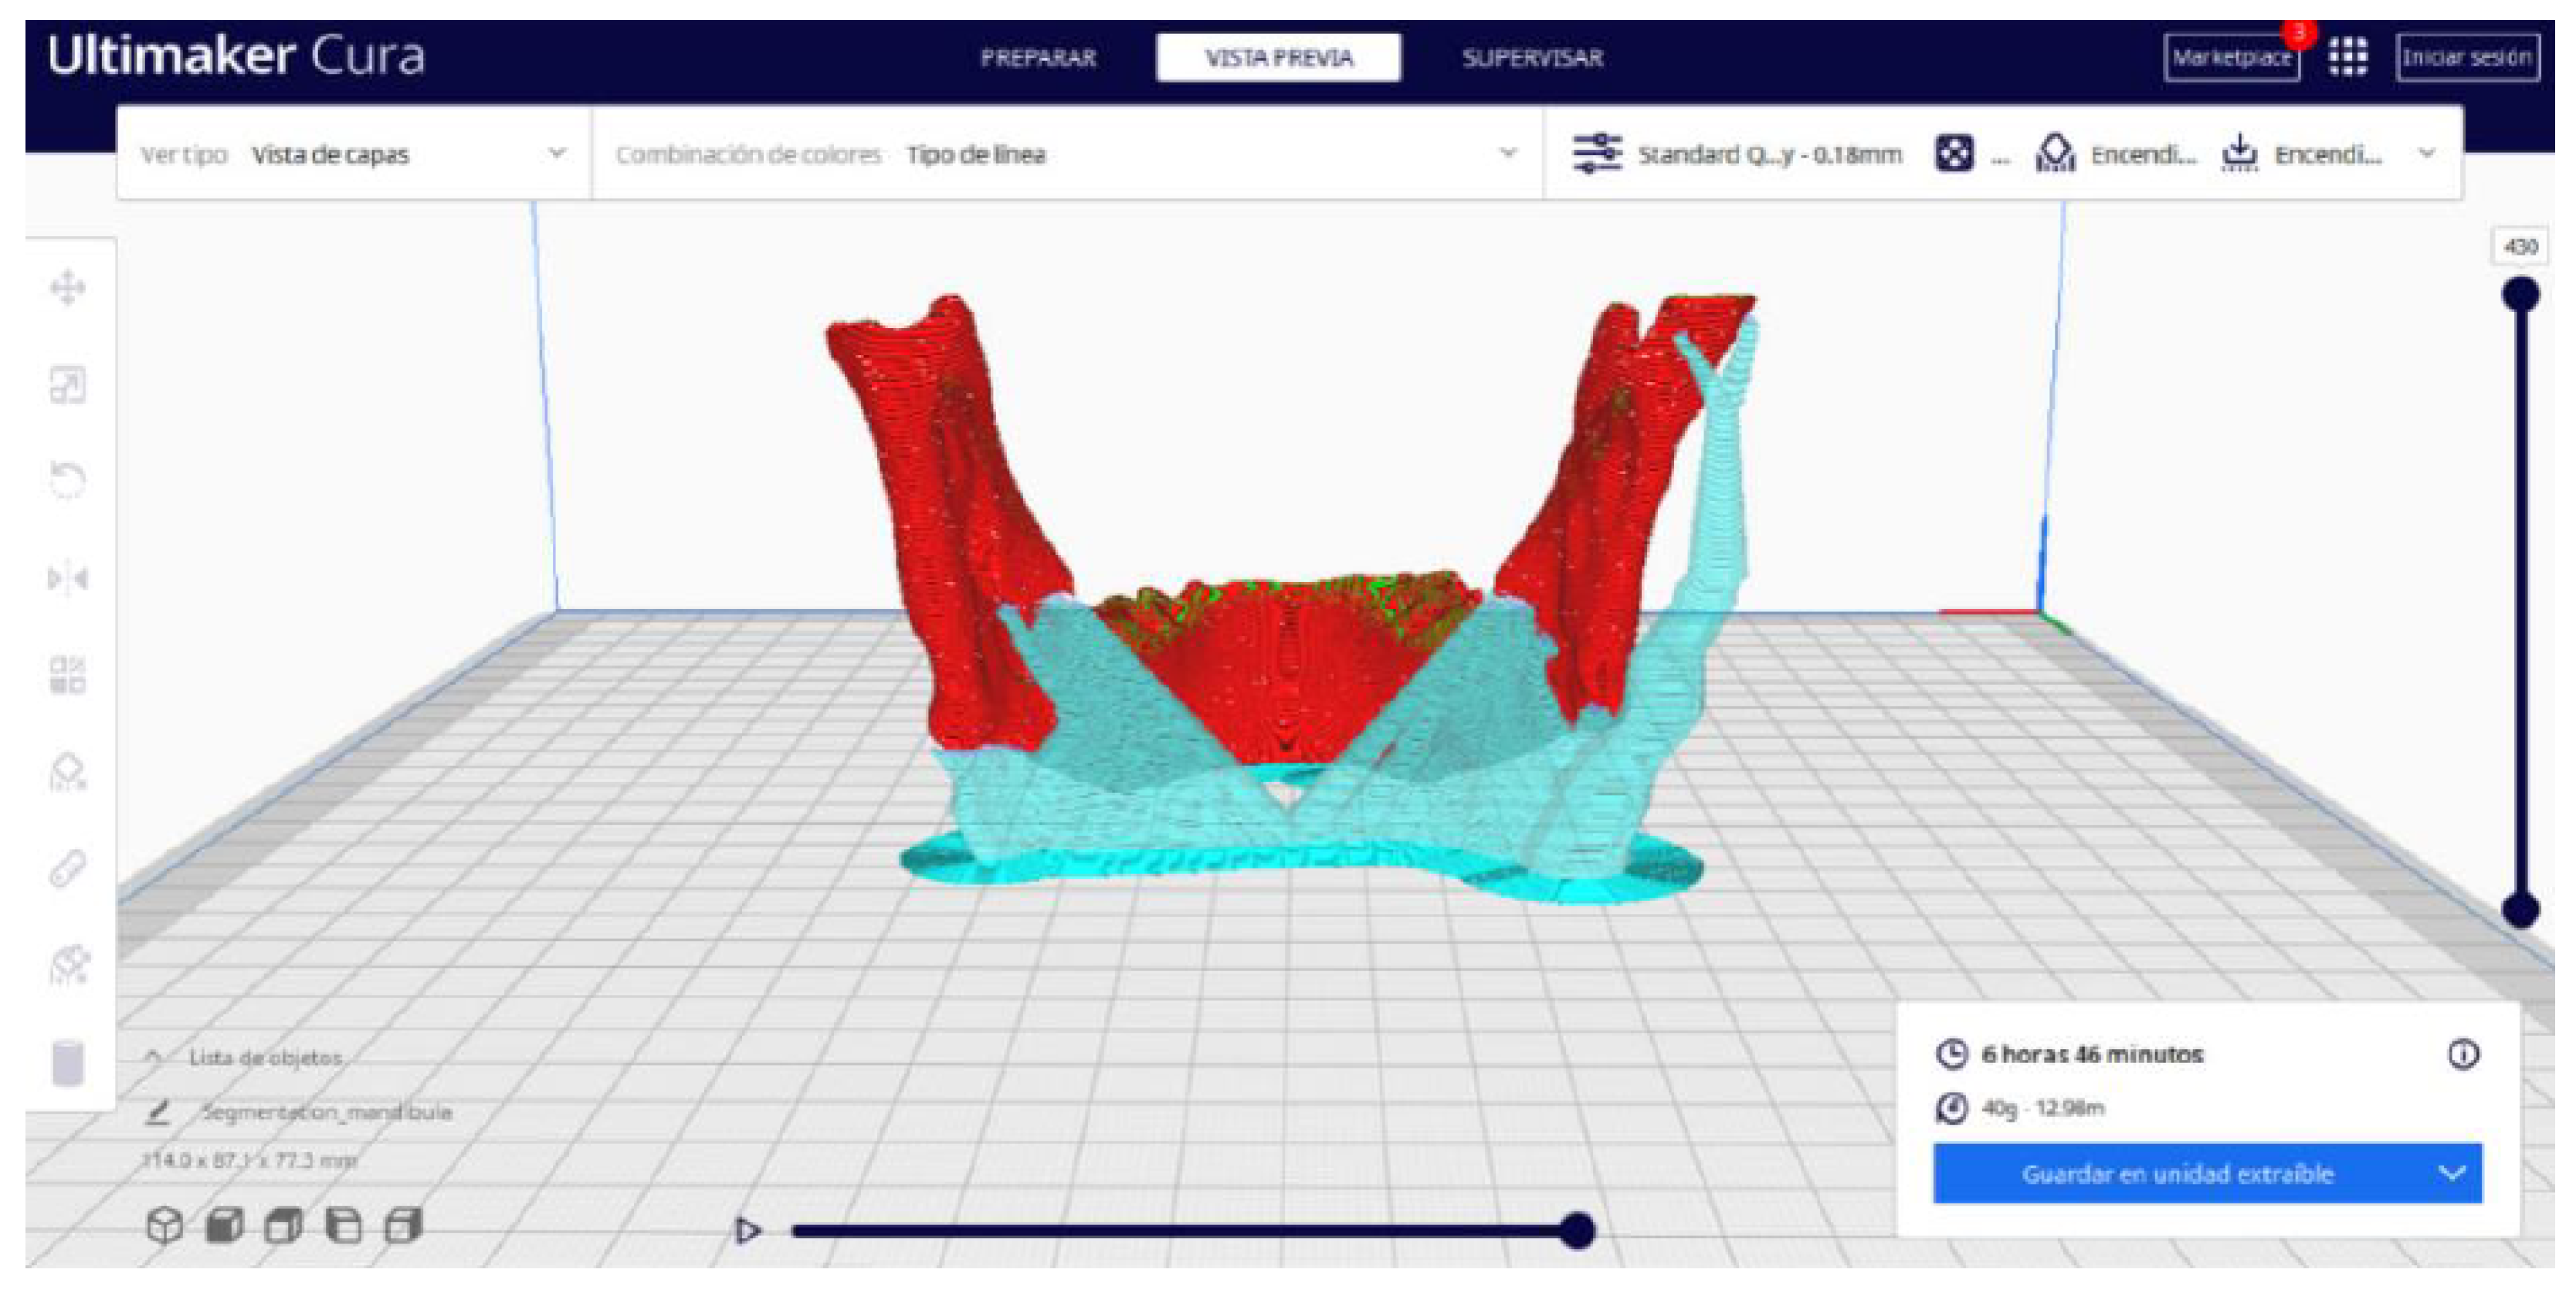

2.2. STL-to-GCODE File Conversion

- Choose the appropriate support structure type and pattern to ensure the successful printing of complex geometries, adjusting the adhesion to the build plate as necessary.

- In order to continue the STL file to GCODE conversion process, select the “Segmentation” option in Ultimaker Cura.

- The segmentation tool provides valuable information such as the estimated model weight and estimated printing time, among other crucial data.

- Once the segmentation is complete, go to the “Preview” option. Here, a sidebar will appear on the right side of the screen, giving you the ability to preview the materialisation process layer by layer, from the base to the top of the model.

3.2. Human Lower Jaw

3.2.2. STL-to-GCODE Files